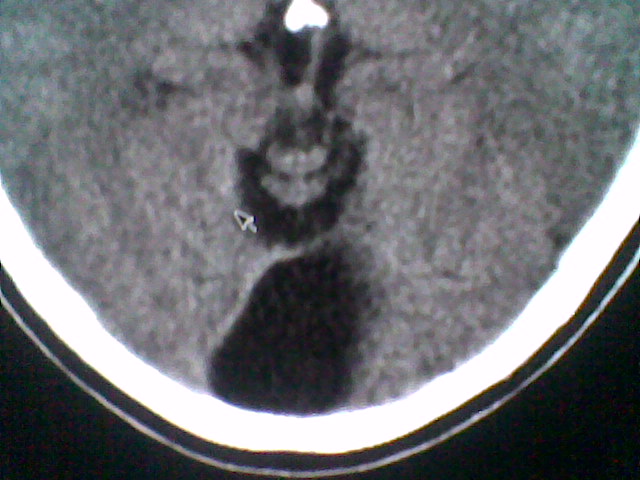

患者,男,头晕4天来诊,要求ct。

大枕大池合并蛛网膜囊肿。

支持 大枕大池合并蛛网膜囊肿。

考虑大枕大池合并蛛网膜囊肿。

有没有dandy-walker综合征的可能?